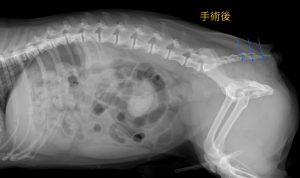

このワンちゃんは、自分の筋肉がそこまで弱っていなかったため、最もシンプルな筋肉と靭帯を縫合する方法を選択して、無事に整復することができました。

術後は思ったように便が出ず心配でしたが、1週間ほどで手術前よりスムーズに排便できるようになりました。これからも、よく食べてよく出して元気でいてね!